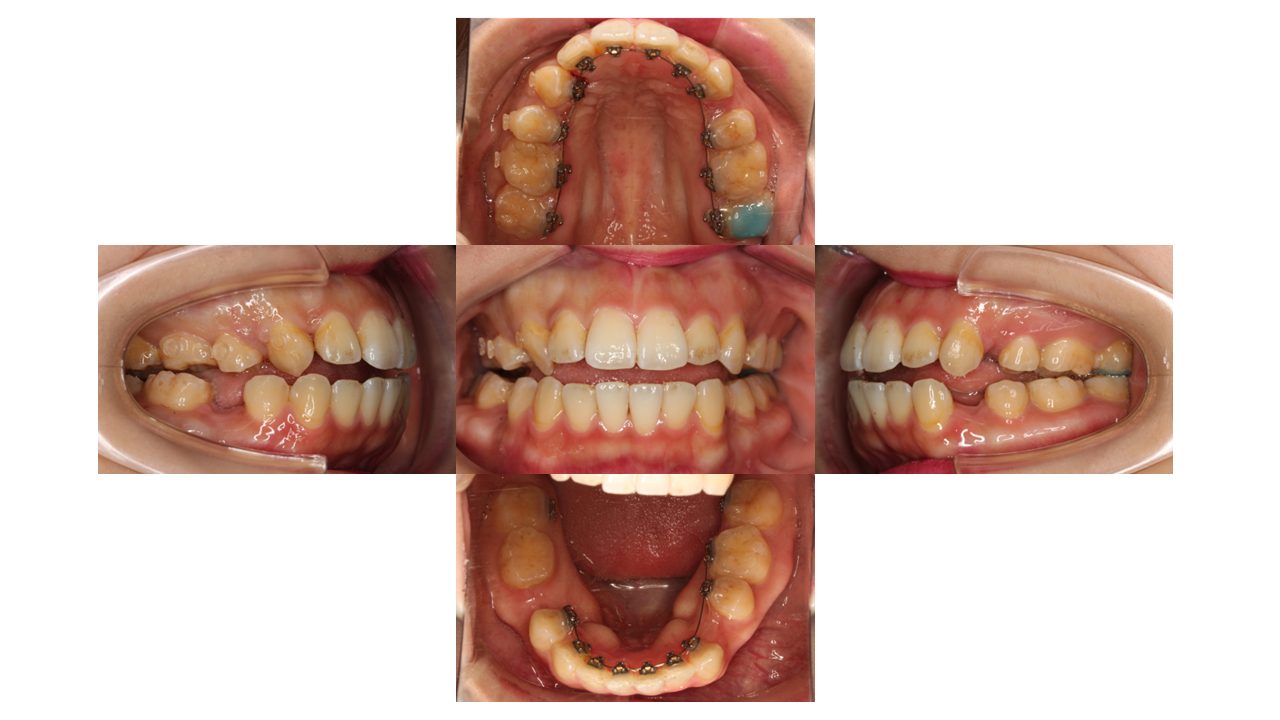

3か月経過の口腔内の状態です。

少しずつ凸凹が改善されてきました。